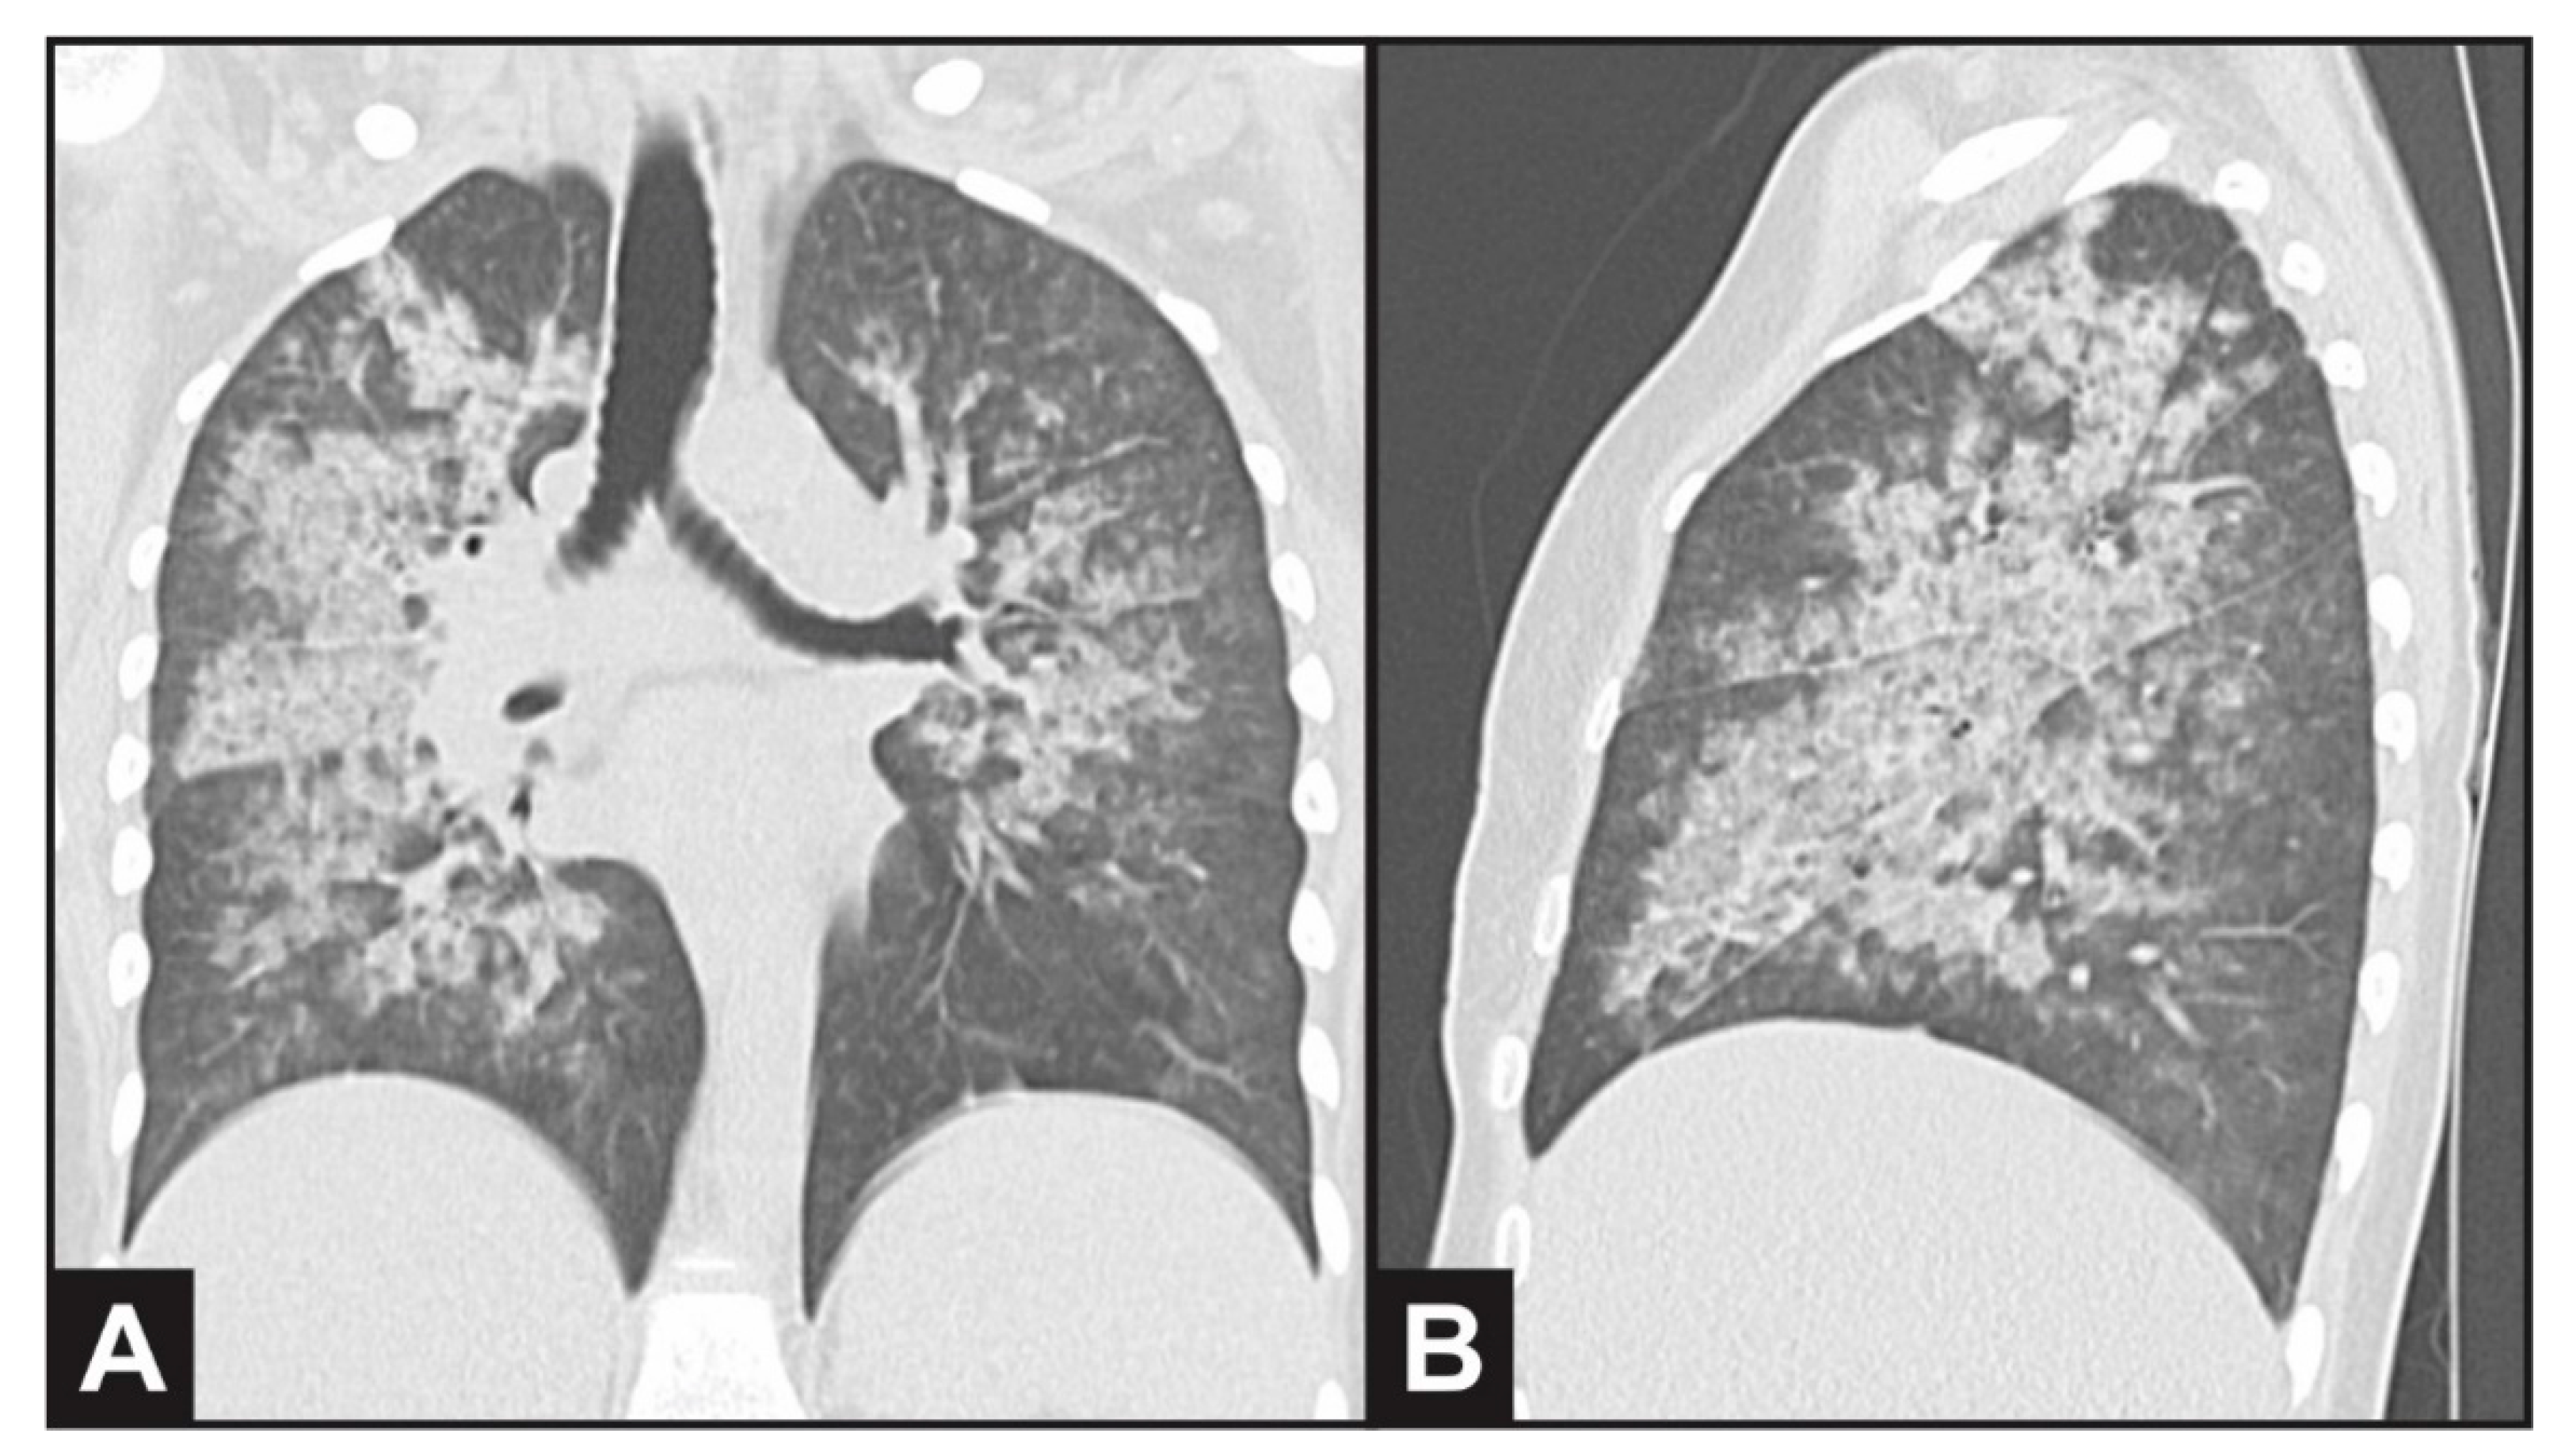

Ultrasound revealed normal-sized kidneys with preserved echogenicity. A chest CT scan evidenced bilateral and diffuse ground-glass opacities (Figure 1), thickening of intralobular septa and luminal filling in the bronchial walls, compatible with alveolar hemorrhage. She was prescribed antibiotics (ceftriaxone and clarithromicin) due to possible bacterial infection. Serum immunodiffusion for fungi was negative (Paracoccidiodes brasiliensis, Aspergillus fumigatus and Histoplasma capsulatum). Bronchial washing results were negative for viruses, bacteria, mycobacteria and fungi, revealing the presence of bloody fluid in the respiratory tract.

Figure 1. Computed thorax tomography evidencing bilateral and diffuse ground-glass opacities in (A) coronal and (B) sagittal plane view, compatible with alveolar hemorrhage.